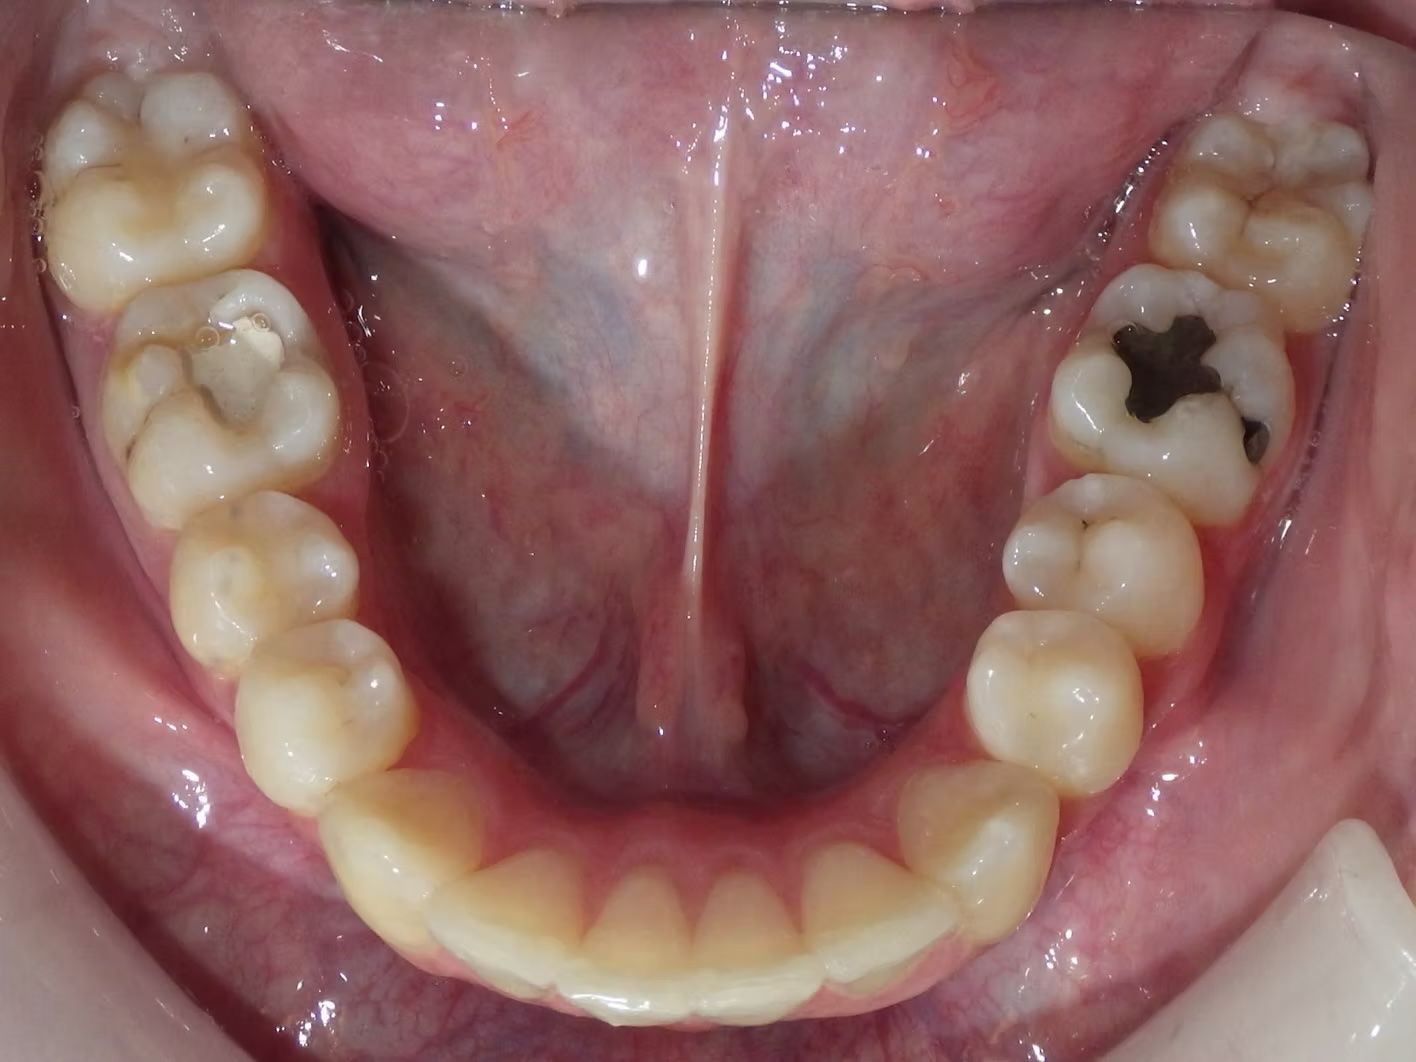

Imset

Imset came to see Dr. Bret because he felt like the upper and lower teeth were too crowded. The lower canines were in cross-bite with the upper teeth and there was significant crowding in the lower arch. He previously had 2 teeth pulled in the top and at the time none in the bottom. This made the top jaw smaller than the lower and the lower teeth didn't have room to fit inside the top teeth. We had 2 lower teeth extracted, and then aligned the upper and lower teeth to fit excellently together- no more crowding!